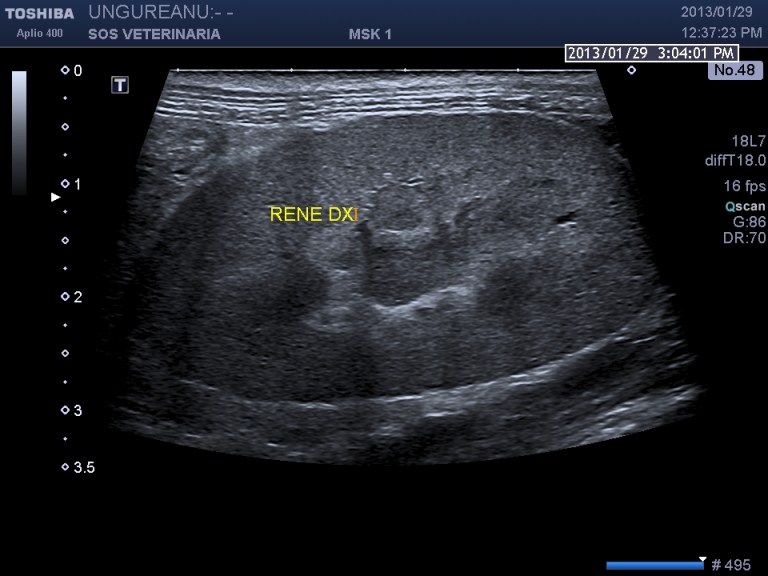

Gatta comune europea 16 aa DSC_8846

evidente la severa  dilatazione delle vie biliari intraepatiche( visualizzabile nelle fasi piu’ avanzate dei processi cronici) ,la massa prende origine dal  coledoco e ha generato nel corso della malattia una progressiva distenzione delle vie biliari extraepatiche che raggiungono gradi di dilatazione abnormi e rimangono riconoscibili per la parete ispessita , come in questo caso possono essere presenti calcoli o calcificazioni della massa .

.Nonostante la gravita’ del processo il soggetto ha convissuto con la malattia diversi mesi